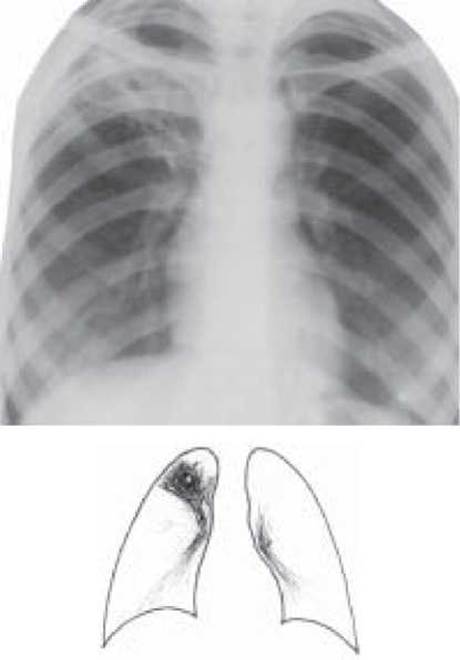

Інфільтративний Туберкульоз легень - специфічний ексудативно-пневмонічний процес, розміром понад 1 см, зі схильністю до швидкого прогресування і розпад (рис. 17). В теперішній час це найбільш розповсюджена форма легеневого туберкульозу і серед вперше діагностованих хворих становить 54,9 %.

Рис. 17. Інфільтративний туберкульоз верхньої частки правої Легені, фаза розпаду. Оглядова рентгенограма

Рентгенологічно для інфільтративного туберкульозу характерним є: тінь понад 1 см в діаметрі, негомогенного характеру, середньої або слабкої інтенсивності, зв'язаної «доріжкою» з коренем, переважно локалізується в I, II або VI сегментах, в центрі інфільтрату порожнина розпаду, а навколо або в інших ділянках легень вогнища бронхогенної дисемінації.